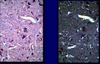

What are giant cells?

- Macrophages fused together to produce larger cells

- caused by foreign bodies or infection with certain bacteria are present

- Large cells with dozens to hundreds of nuclei

- Seen in granulomatous inflammation

What are the three types of giant cell?

- Langhan’s Giant Cells

- Touton Giant Cells

- Foreign Body Giant Cells

Where are Langhans giant cells normally found?

- nuclei are arranged around the periphery of the giant cell

- normally seen in tuberculosis

- the immune system find the TB bacteria difficult to resolve

What do foreign body type giant cells look like and where are they normally found?

- nuclei are arranged randomly in the cell

- often seen when there is a hard to digest foreign body

- if the foreign body is small it can be phagocytosed by the giant cell and seen within it.

- if it is large the foreign body giant cell sticks to its surface